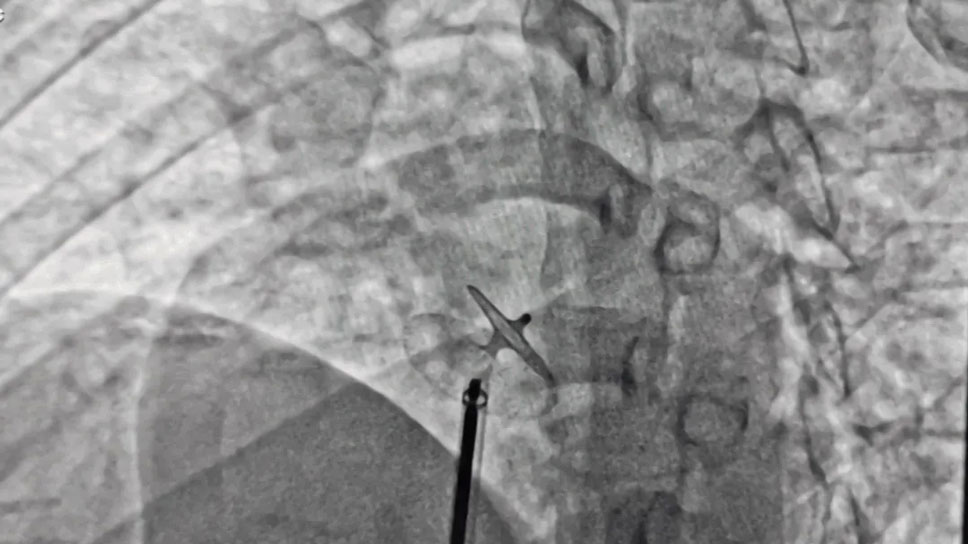

患者,女性,31岁,反复胸痛、气短、头晕,往返省州多家医院,病因反复不明,多种症状仍然存在,已严重影响生活,来我院后行冠脉造影及胸部增强CT均未见明显异常,心脏彩超提示“卵圆孔未闭”,初步锁定为卵圆孔未闭所致。患者入住心内科后,副院长张承中立即会同张宏伟教授对病例进行会诊讨论后一致认为,该患者最好行卵圆孔介入封堵术。经充分沟通,患者及其家属重拾希望,积极要求行手术治疗。经术前充分准备,手术在张宏伟、张承中两位专家的带领下于2021年08月17日进行,手术过程顺利,术后复查心脏彩超及右心声学造影,结果提示“心房水平静息与负荷状态下均未见右向左分流”,患者术后安返病房。

随着医疗技术的进步,尤其是心导管技术的发展,相当一部分左向右分流先天性心脏病(如动脉导管未闭、房室间隔缺损、室间隔缺损)可经介入治疗根治。同时经皮介入PFO封堵术却具有安全、有效、创伤小的优点。手术从大腿根部腹股沟区穿刺股静脉,循人体自身大血管路径(股静脉→髂外静脉→髂总静脉→下腔静脉→右心房)将封堵器送达并固定于未闭的卵圆孔处,PFO封堵术主体部分耗时约5-10分钟,术后仅在大腿根部留有针眼大小穿刺伤口,术后半年PFO平均闭合率可超过98%。